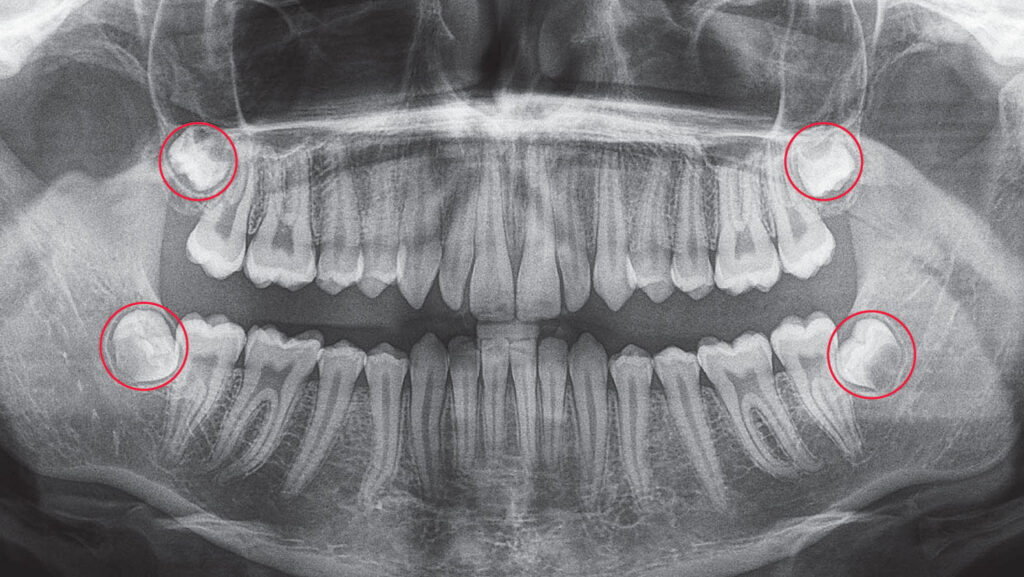

- Thăm khám nha khoa định kỳ

- Chụp X-quang hoặc CT Cone Beam 3D để kiểm tra vị trí răng khôn, mức độ xương hàm và khả năng ảnh hưởng đến răng khác.

- Chụp X-quang CT Cone Beam 3D: Xác định chính xác vị trí, hướng mọc và cấu trúc xương quanh răng khôn.

- Chụp CT Cone Beam 3D xác định vị trí, hướng mọc, độ nghiêng, số chân răng và mối quan hệ với dây thần kinh, xoang hàm, răng số 7.